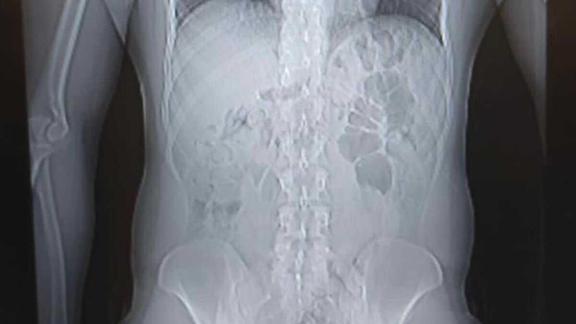

Öte yandan, İstanbul Havalimanı'nda İran'dan gelen 3 turist şüphe üzerine durduruldu. Yapılan aramalarda şüphelilerin midesinde toplam 3 kilo ağırlığında 320 kapsül eroin maddesi tespit edildi. Gözaltına alınan 3 İran uyruklu şüphelinin midesinde bulunan 320 adet kapsül eroin maddesi çıkartılırken, şüphelilerin emniyetteki işlemlerinin sürdüğü bildirildi. Operasyon anları kameraya yansırken, ele geçirilen uyuşturucu maddeler İstanbul Emniyet Müdürlüğü'nde sergilendi.